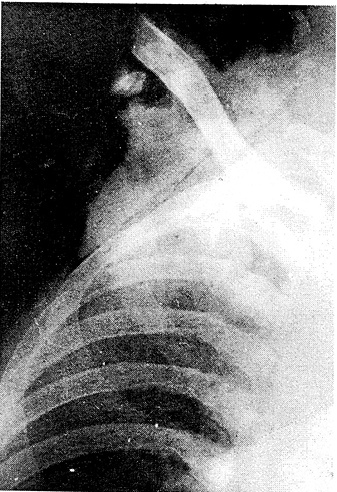

Больной взят в операционную. Начаты реанимационные мероприятия: обезболивающие, сердечно-сосудистые средства, инфузионная терапия. После определения группы крови перелито 400,0 мл одногруппной крови. После улучшения общего состояния и выведения из шока рана обильно промыта растворами антисептиков, нежизнеспособные ткани щадяще иссечены. Ключица вылущена в грудинно-ключичном сочленении. После этого произведено лигирование в ране подключичных артерий и вены проксимальнее; дистальные их участки, перевязанные веревкой, отсечены. Стволы плечевого нервного сплетения в ране найдены не были; по-видимому, отрыв их произошел на уровне первичных стволов, центральнее. Повреждения плевры не выявлено. Рана закрыта местной кожной пластикой. Установлена проточная дренажная система. Наложена асептическая повязка. Выполнена контрольная рентгенография (рис. 2).

Рис. 2. Рентгенограмма больного Н. после операции.